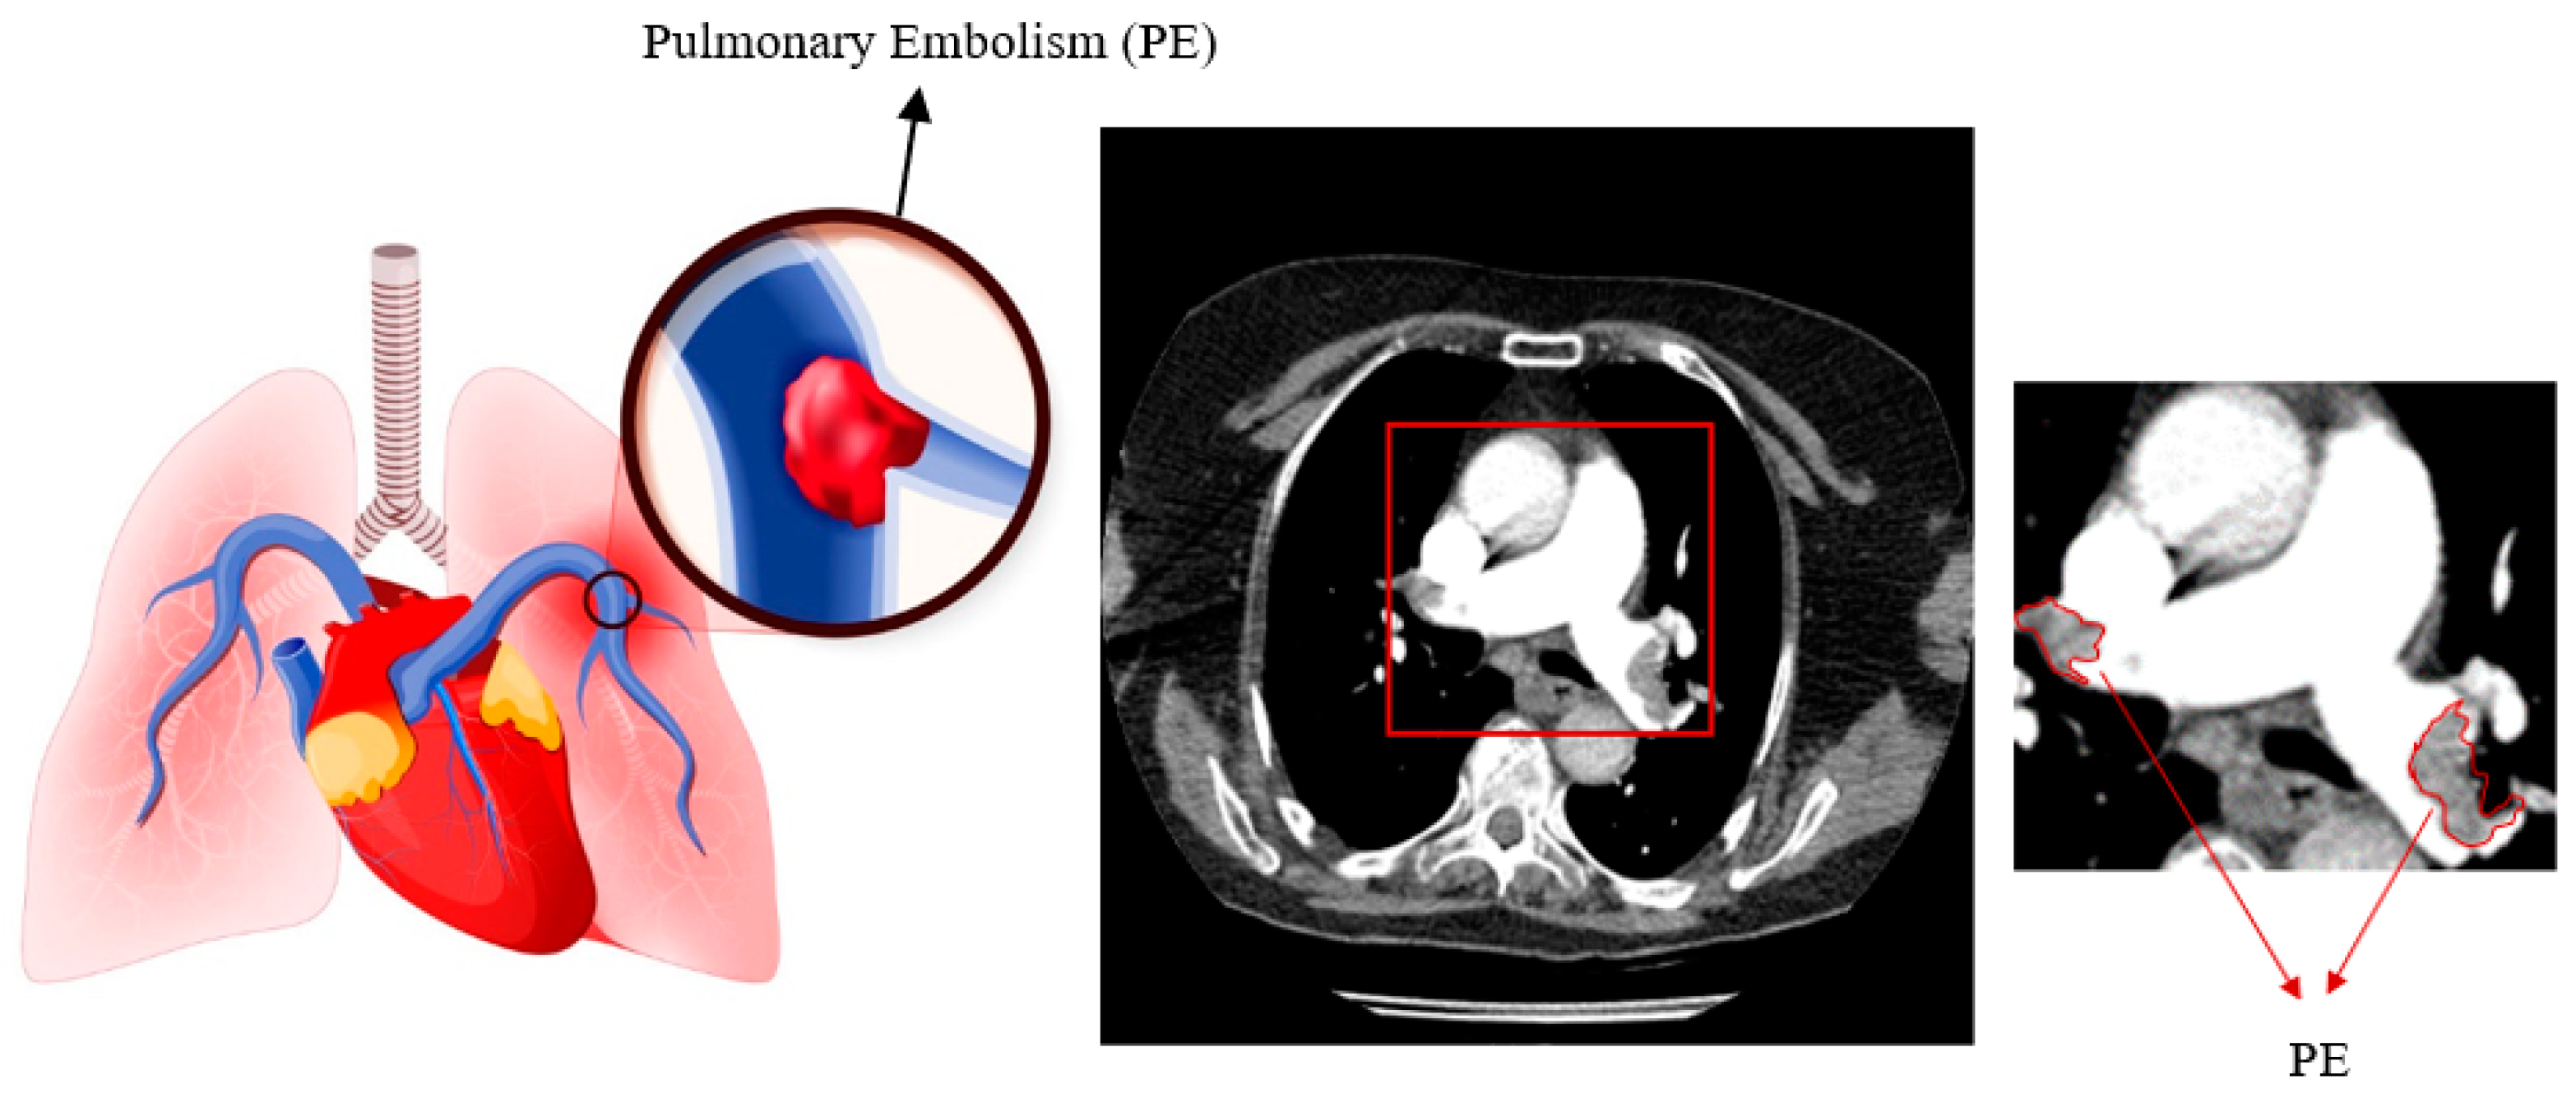

An Enhanced Mask R-CNN Approach for Pulmonary Embolism Detection and Segmentation

1. Introduction